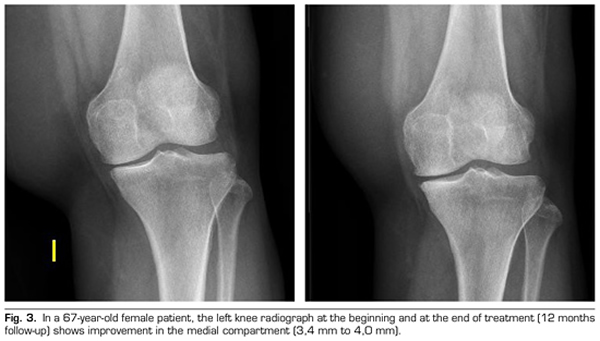

Regarding the radiological variables, when evaluating 53 out of the 115 patients who completed one year of follow-up after ozone treatment, it was observed that the internal compartment increased significantly by 4.12 ± 1.41 mm to 4.4 ± 1.35 mm (p = 0.0008) and the external compartment increased from 6 ± 1.37 to 6.16 ± 1.4 mm (p = 0.0753) (Table II). Two clinical cases are presented as a sample of the radiological change in the internal and external compartments (Figures 2 and 3).

After a year of follow-up with radiological controls on 53 out of the 115 patients in the study, ozone (O2-O3) has been able to increase the minimum joint space of the medial compartment (from 4.12 to 4.44 mm) and the lateral compartment (from 6.0 to 6.16 mm), reversing knee osteoarthritis in our case series. This finding suggests the disease modifying effect of ozone (O2-O3) on knee osteoarthritis, findings that is consistent with the recently reported by Fernández-Cuadros et al. (9).